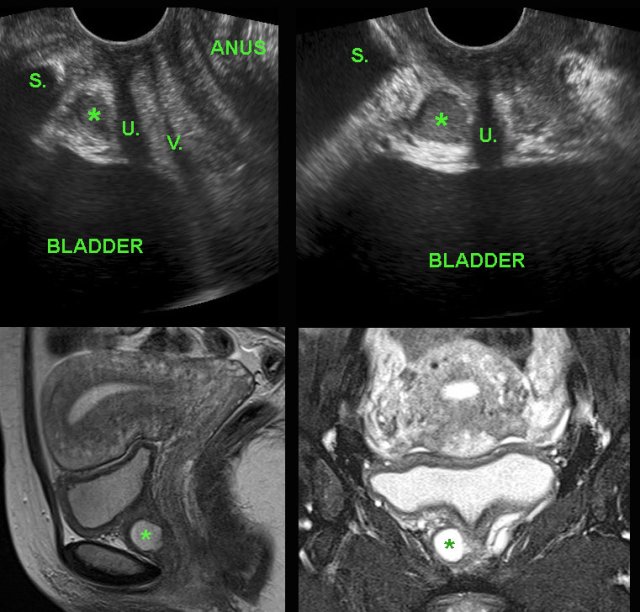

Urethral diverticulum demonstrated by TVUS. Urethral diverticulum demonstrated by TVUS.

Urethral diverticulum

Recurrent lower urinary tract infections may be caused by intermittent obstruction / infection of an urethral diverticulum. In this young woman, TVUS (with the probe in vulvar position) detected a large, inflamed urethral diverticulum (*) right and anterior of the urethra (U.) (V. and S. = vagina and symphysis).

Confirmation by sagittal and coronal MRI.